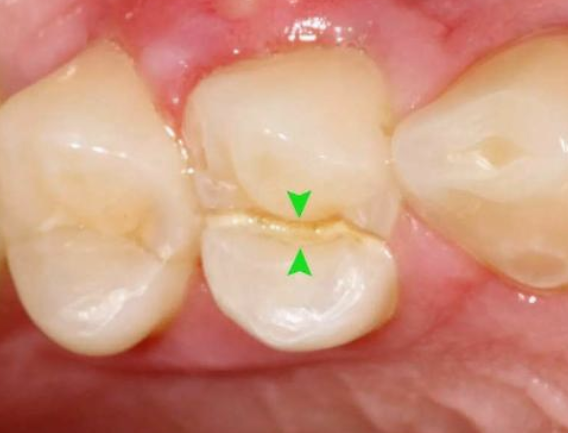

真实案例:下面这幅图片就是一个牙科医生发出来的一个患者的牙,之前做了“根管治疗”后,没有及时做“牙冠”,导致吃东西时把原来做过‘根管治疗’的牙直接劈成了2半,这不是既麻烦又难受?后悔都来不及了!!